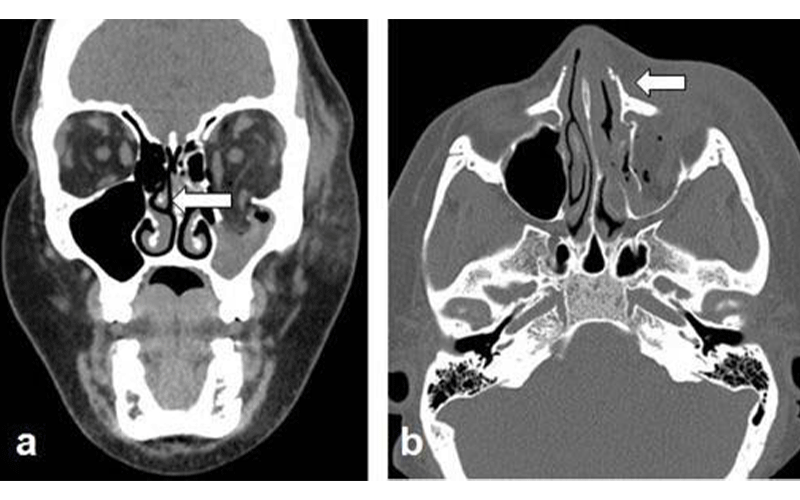

“During the pandemic, victims experienced more injuries to the chest and abdomen compared to prior years,” said coauthor Babina Gosangi, MD, assistant professor of radiology at Yale New Haven Health in New Haven, Connecticut, and former emergency radiology fellow at Brigham and Women’s Hospital. “For instance, one victim sustained multiple bilateral rib fractures with right pneumothorax and bilateral lung contusions—requiring hospital admission for more than 10 days—after she was repeatedly punched in the chest. Another victim was stabbed in the abdomen and had lacerations to the liver and kidney.”

By recognizing high imaging utilization, location and imaging patterns specific to IPV, old injuries of different body parts, and injuries inconsistent to provided history, radiologists can identify victims of IPV even when the victims are not forthcoming.